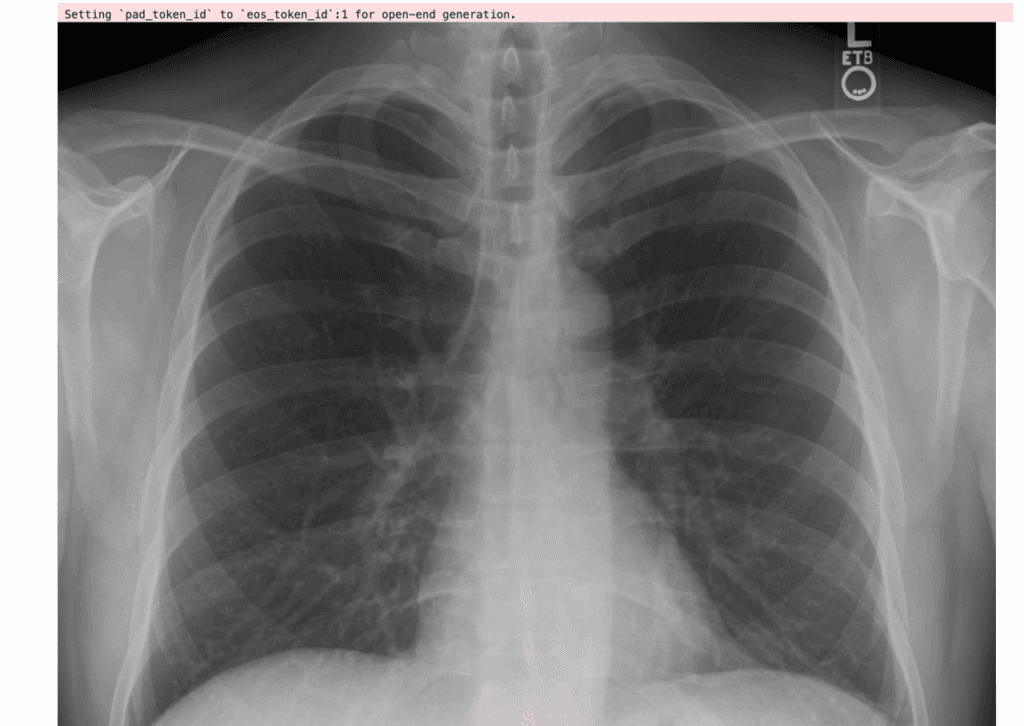

Prompt: “Describe this X-ray”

Here’s the input image: